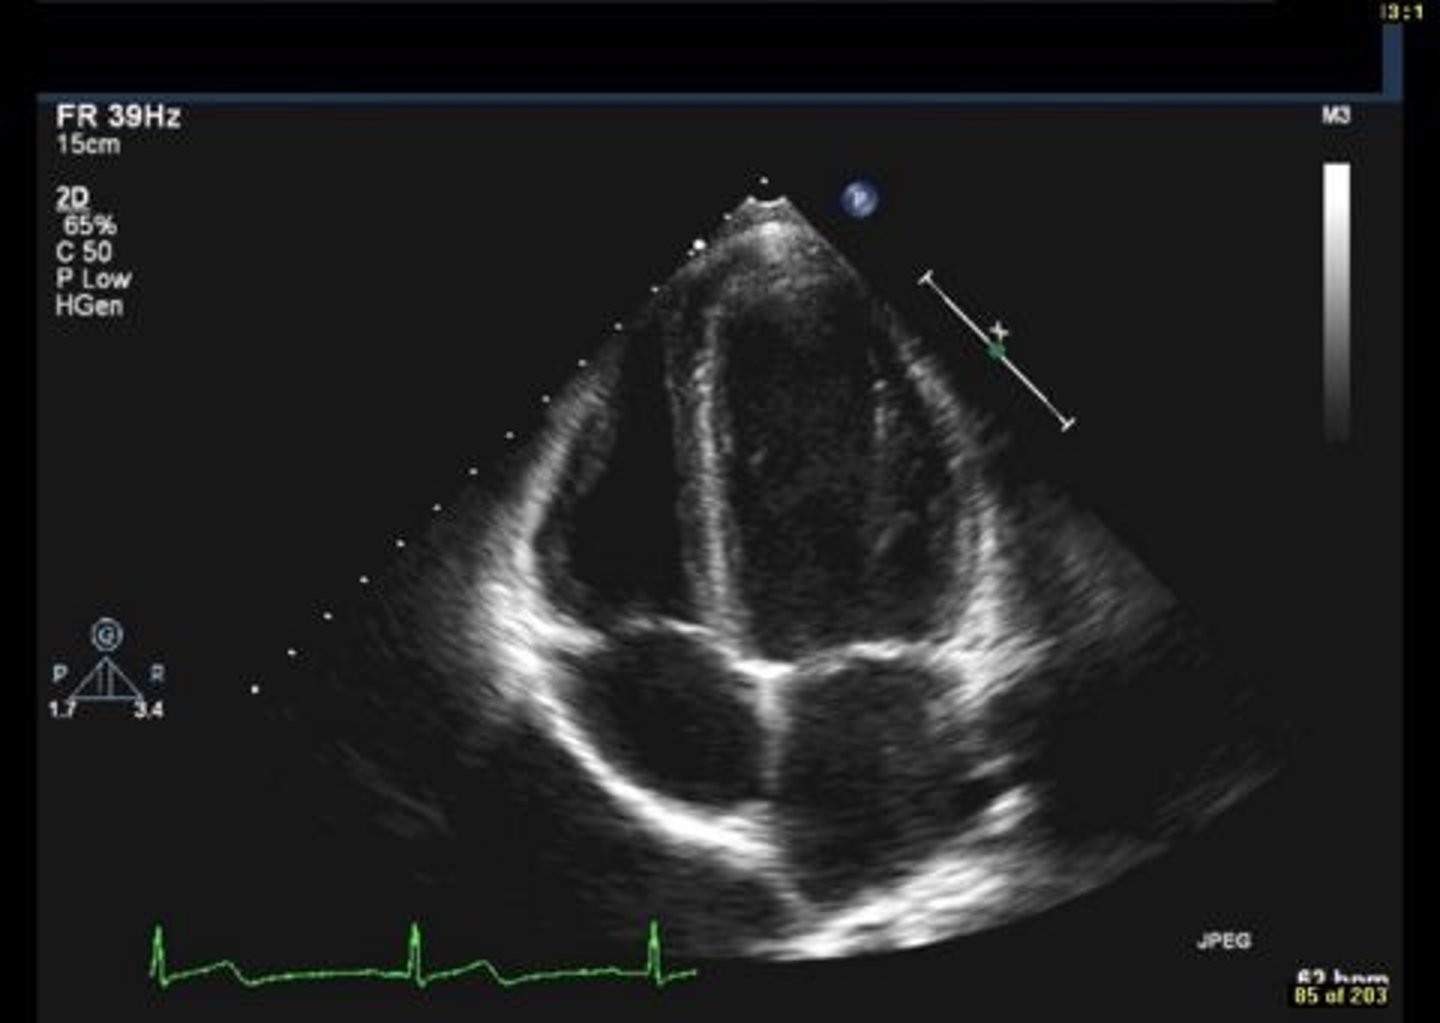

MV PLAX (top leaflet)

AMVL

MV PLAX (bottom leaflet)

PMVL